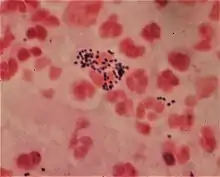

Gram staining differentiates bacteria by the chemical and physical properties of their cell walls. Gram-positive cells have a thick layer of peptidoglycan in the cell wall that retains the primary stain, crystal violet. Gram-negative cells have a thinner peptidoglycan layer that allows the crystal violet to wash out on addition of ethanol. They are stained pink or red by the counterstain,[3] commonly safranin or fuchsine. Lugol's iodine solution is always added after addition of crystal violet to strengthen the bonds of the stain with the cell membrane.

After decolorization, the gram-positive cell remains purple and the gram-negative cell loses its purple color.[17] Counterstain, which is usually positively charged safranin or basic fuchsine, is applied last to give decolorized gram-negative bacteria a pink or red color.[3][18] Both gram-positive bacteria and gram-negative bacteria pick up the counterstain. The counterstain, however, is unseen on gram-positive bacteria because of the darker crystal violet stain.